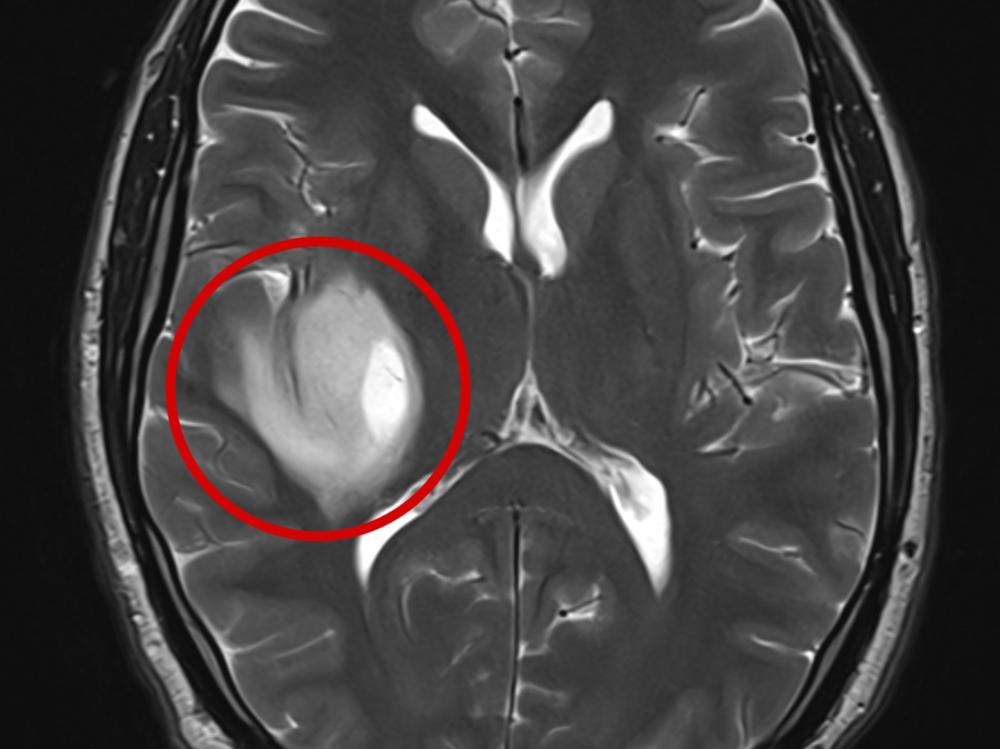

I never imagined writing this, but here I am—30 years old with a Glioma brain tumor.

In August 2024, my life changed forever. One moment, I was baking cookies; the next, I was on the floor. Hours later, I was in a hospital bed being told I had a tumour deep in my brain on my right basal ganglia. Surgery or biopsy risks paralysis or death, and I’ve always feared chemotherapy and radiation, so I'm looking at other options to help.